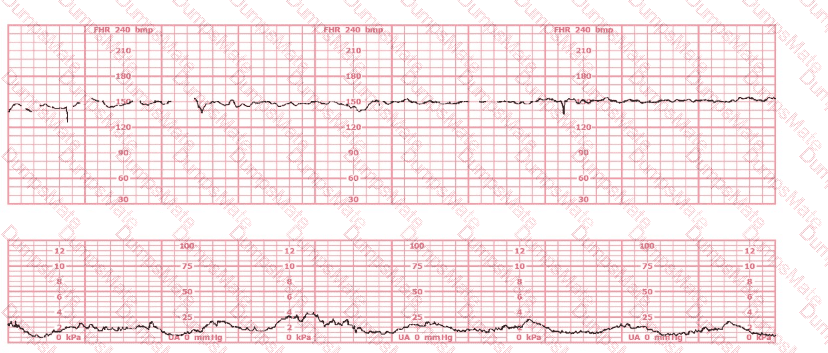

Questions 12

(Full question statement)

The fetal heart rate tracing shown is obtained upon the woman's admission to labor and delivery. This tracing is most consistent with what maternal condition?

EFM Question 12

Options:

A.

Eisenmenger's syndrome

B.

Sickle cell anemia

C.

Systemic lupus erythematosus